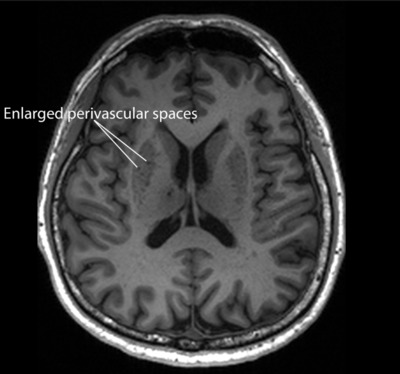

Blood vessels in the brain are surrounded by perivascular spaces where toxic waste in the brain, such as beta amyloid and tau proteins, drains into and is cleared. If these drains get clogged because the brain’s system of clearing toxic waste is not working efficiently, they form enlarged perivascular spaces, which can be seen on magnetic resonance imaging (MRI) scans. But it was not previously clear if this condition was also linked to Alzheimer’s disease.

The researchers analysed the MRI scans of the participants and found that those with mild cognitive impairment tend to have more enlarged perivascular spaces compared to the other participants. The scientists also took seven measurements based on specific biochemicals in the participants’ blood, including beta amyloid and tau proteins, whose presence is a warning sign that a person has Alzheimer’s.

As revealed in the journal Neurology, the presence of clogged drains in the brain was linked to four of the seven measurements. So, people with enlarged perivascular spaces are likely to have more amyloid plaques, tau tangles and brain cell damage in their brains than normal, and are thus at higher risk of developing Alzheimer’s.

“The findings carry substantial clinical implications,” said Associate Professor Nagaendran Kandiah, who led the study. “Although white matter damage is more widely used in clinical practice to evaluate for dementia, as it is easily recognised on MRI scans, our results suggest that enlarged perivascular spaces may hold unique value in detecting early signs of Alzheimer’s disease.”

“Since these brain anomalies can be visually identified on routine … MRI scans performed to evaluate cognitive decline, identifying them could complement existing methods to detect Alzheimer’s earlier, without having to do and pay for additional tests,” Kandiah noted.

“The study’s findings are intriguing as they demonstrate that both diseases do interact in a synergistic manner,” Chong said. So, if a doctor orders an MRI brain scan to evaluate a patient’s cognitive symptoms and notices that the scan shows markers of cerebrovascular diseases, such as enlarged perivascular spaces, the clinician should not assume the patient’s cognitive impairment is due only to blood vessel problems.